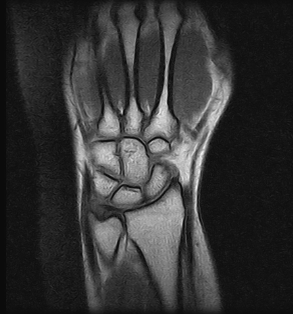

Ressonâncias Magnéticas Punho

Fazemos ressonâncias magnéticas punho utilizando a mais alta tecnologia disponível, ideal até mesmo para pacientes que sofrem com a claustrofobia.